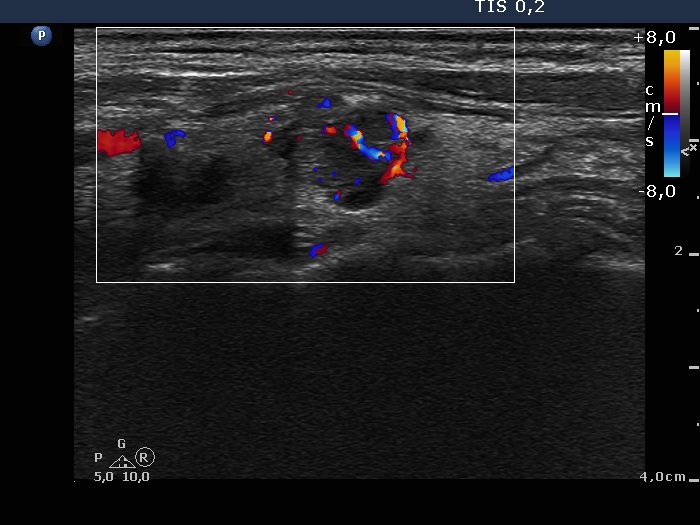

Ethanol sclerotherapy: other examples - Case 2: treatment of a recurrent nodule

Two years after the therapy (ultrasonographic picture 4)

Right lobe, longitudinal scan, color Doppler mode. The vascularization is increased.